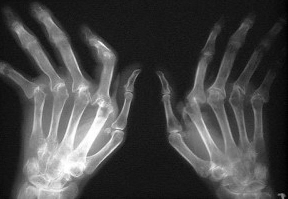

Кроме того, рентгенография обнаружит асимметричные очаги поражения суставов. А еще в ходе диагностики можно найти значительное повышение IgA, причем более значительное, чем при стандартной серопозитивной форме.

Основным методом диагностики при вышеописанном артрите будет рентгенография. При этом для точной постановки диагноза проводить данное исследование нужно далеко не один раз, а на протяжении длительного периода (6-и недель и более).

Врач будет отслеживать постепенное поражение суставов, а обращаться в таком случае нужно к специалисту-ревматологу.